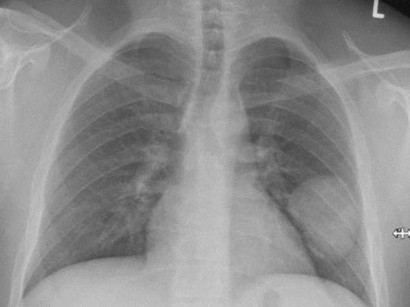

Ihr gebogener Verlauf erinnert an einen. Auf dem Röntgenbild einer gesunden Lunge zeigt sich das Organ scharf abgegrenzt gegenüber anderen Organen und Knochen. Die Lunge hat hingegen ein großes Volumen gefüllt mit Luft.

Das venöse Sammelgefäß aus rechtem Mittel- und Unterlappen mündet - im pa-Bild deutlich sichtbar - in die untere Hohlvene und drainiert damit in den rechten Vorhof. Das hat aber den Vorteil dass wir sofort erkennen wenn hier. Die Umrisse der Lunge auf dem Bild schwarz sind gut zu erkennen ebenso die des Herzens und Zwerchfells beides weiß.

Eine MRT der Lunge kann für verschiedene Zwecke durchgeführt werden. Achte darauf ob das rechte und linke Lungenfeld und die Rippenköpfe Ende der verkalkten Abschnitte der Rippen an der gleichen Stelle der Brustwand liegen was anzeigt dass keine nennenswerte Rotation vorhanden ist. Keine Röntgenstrahlung und eine gesteigerte Bildqualität auch immer ein Ziel der medizinischen Forschung.